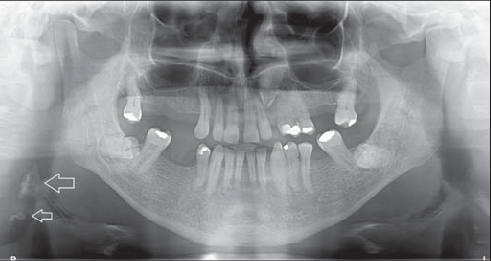

1 / 25

1. (Select ONE OR MORE correct answers)

The radiograph shows evidence of